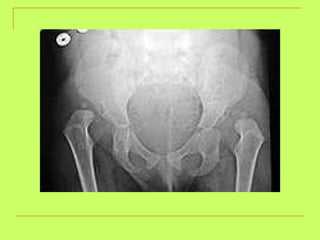

What is the age ? From4-6 Open ischial ramus(less than6) >4years (ossific center at greater trochanter) <15years (opened triradiate suture)

What is the age ? >4 y (ossific center at greater trochanter)<15 y  (triradiate suture is opened )

Age from hip bone examination: Two pubic rami of the hip  (6y) Suture at the acetabulum  (15y). Ischeal tuberosity with the ischium  (21y). Iliac crest with the ilium  (23y).

Age from hipbone examination: Two pubic rami of the hip (6y) Suture at the acetabulum (15y). Ischeal tuberosity with the ischium (21y). Iliac crest with the ilium (23y).